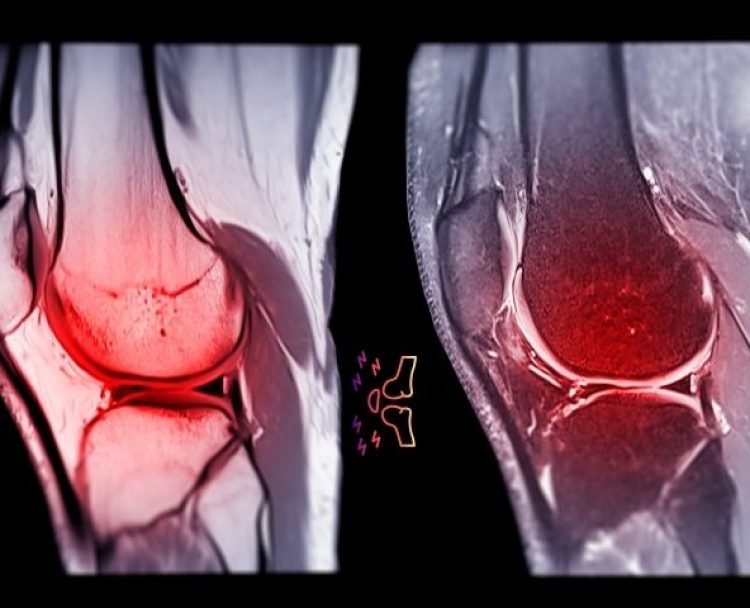

Sports Injury and Arthroscopy

Sports injuries can significantly impact your life. Dr Bajaj specialises in diagnosing and treating sports-related injuries using Arthroscopy to ensure a swift return to your favourite activities.